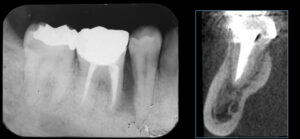

頻繁に奥歯のまわりが腫れてくるとのことでご来院されました。初診時は応急的に抗菌薬で炎症を抑えて、後日現状を詳しく精査していきました。

2本あるうちの手前の1本の根っこが縦に割れてしまっている状態でした。折れた手前の根だけ抜歯して、奥の根を残しても余分な負荷がかかって予後が良くないことは自明です。患者様との相談の結果、奥歯を抜歯してインプラント治療をしていく運びとなりました。まず周囲組織に負担がかからない方法で慎重に抜歯していきます。